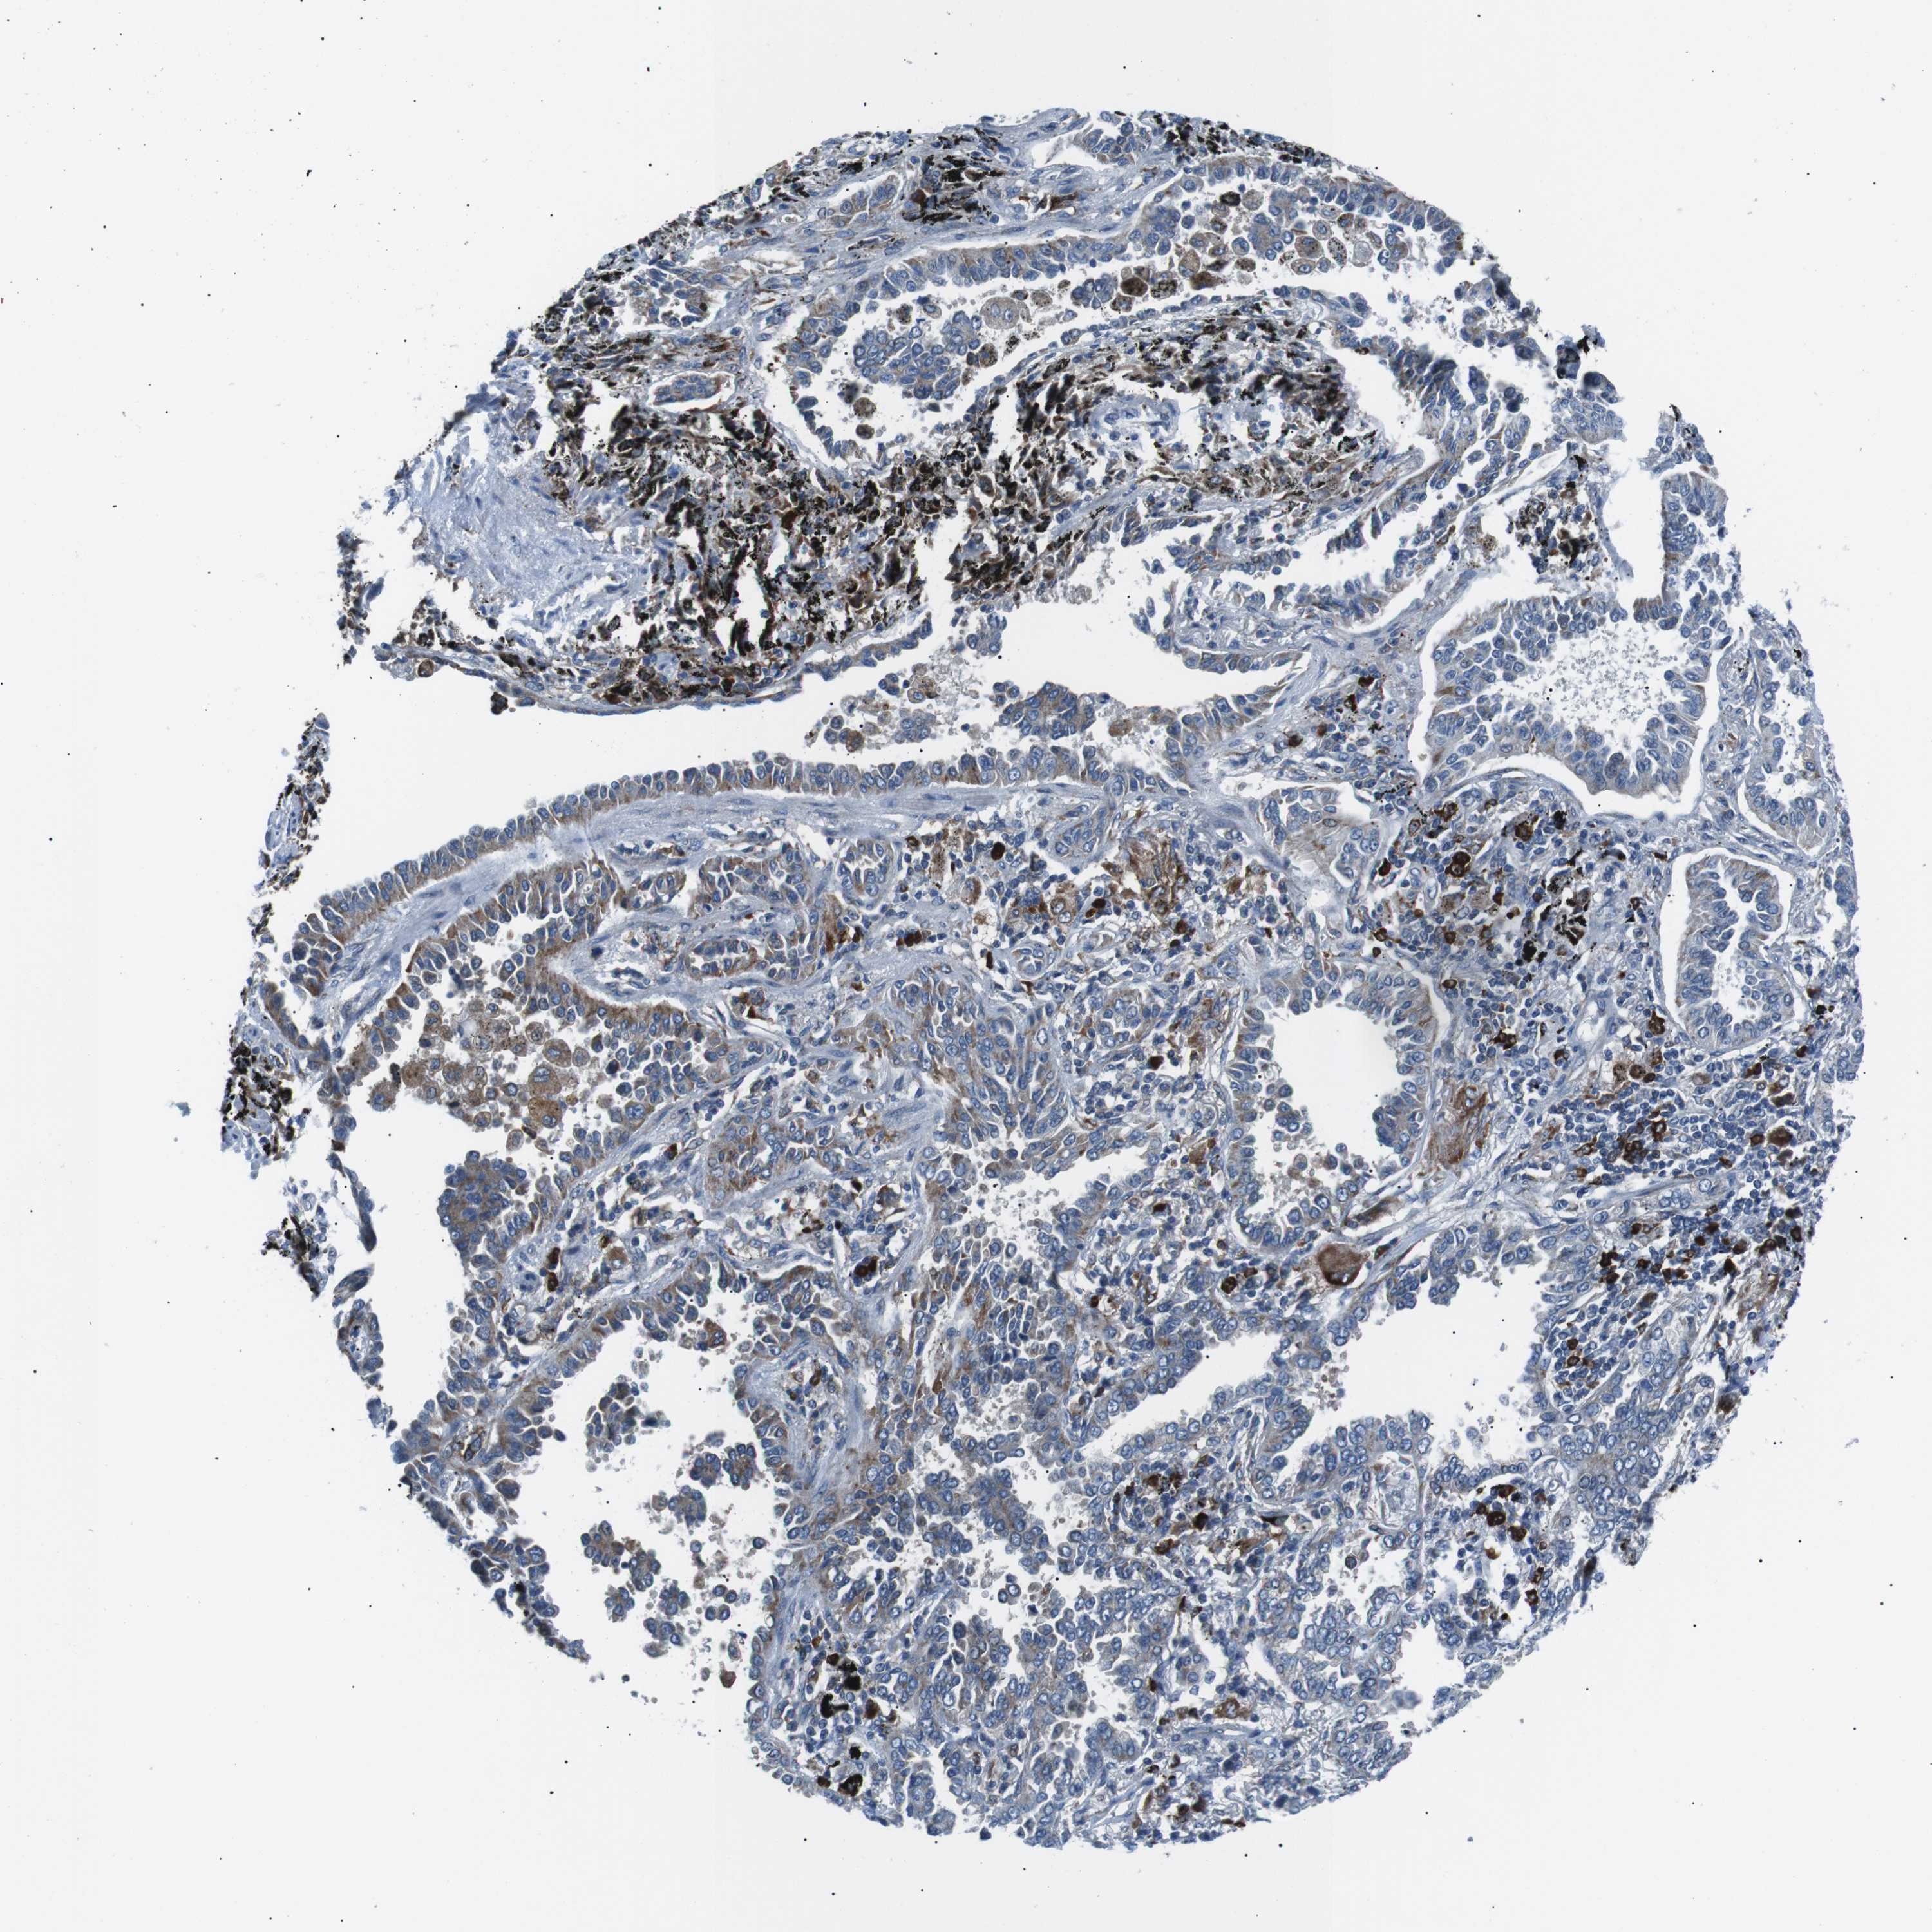

CANCER LUNG CANCER Show tissue menu

LUAD TCGA LUAD VALIDATION LUSC TCGA LUSC VALIDATION PROTEIN LUAD CPTAC PROTEIN LUSC CPTAC PROTEIN EXPRESSION